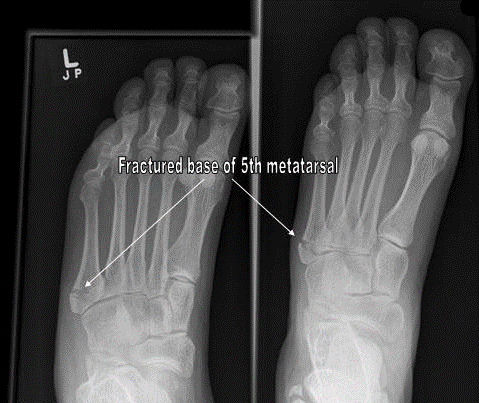

Lawrence 等根据骨折部位把第五跖骨近端骨折分为3区(最常用):

• Ⅰ区:骨折是跖骨粗隆部撕脱骨折,发生率最高;

• 区:骨折是干骺端与骨干连接部骨折,又称Jones骨折,因血运原因容易发生不愈合;

• III区:骨折是跖骨干部的疲劳骨折,多见于运动员